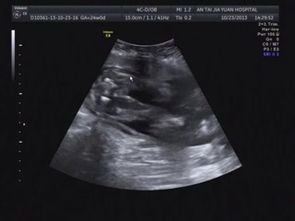

脾臟B超、肝臟和腎臟B超檢查前:一般無須特別準(zhǔn)備,但最好是空腹進(jìn)行。病人如同時(shí)要作胃腸、膽道X線造影時(shí),超聲波檢查應(yīng)在X線造影前進(jìn)行,或在上述造影3天后進(jìn)行。

指導(dǎo)意見: 如需用區(qū)別病變是否在盆腔,檢查前要保持膀胱充盈。作腹腔器官檢查時(shí),遇腹腔氣體過多或有便秘的患者,醫(yī)生可能囑檢查前日晚服緩瀉藥,或在檢查前灌腸,患者應(yīng)當(dāng)認(rèn)真配合。

如檢查盆腔的子宮及其附件、膀胱、前列腺等臟器時(shí),檢查前需保留膀胱尿液,可在檢查前2小時(shí)飲開水1000毫升左右,檢查前2-4小時(shí)不要小便。